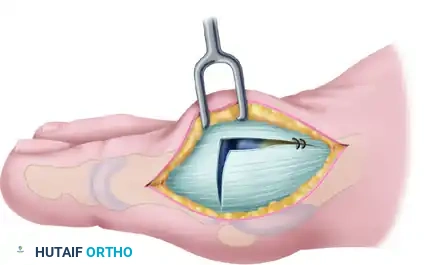

Step 3: The Inverted-L Capsulotomy

To maximize the effectiveness of the revision capsular imbrication, an extensive dorsal exposure is required. Commonly, a thin slip of accessory extensor tendon is visible; this serves as a helpful anatomical landmark. If absent, locate the dorsal and medial juncture of the rounded distal first metatarsal head.

Using either the medial aspect of the accessory tendon or the dorsomedial border of the first metatarsal as a starting point, perform an inverted-L capsulotomy. Complete a capsular-periosteal excision from the first MTP joint line extending proximally to the junction of the middle and distal thirds of the metatarsal.

Begin the transverse limb of this incision exactly at the joint line. Applying axial traction on the hallux helps to identify the distal edge of the metatarsal head, preventing inadvertent scoring of the articular cartilage with the scalpel. The transverse limb extends from dorsal to plantar through the capsule and the conjoined capsular-abductor hallucis tendon insertion, terminating 2 to 3 mm medial to the tibial sesamoid.